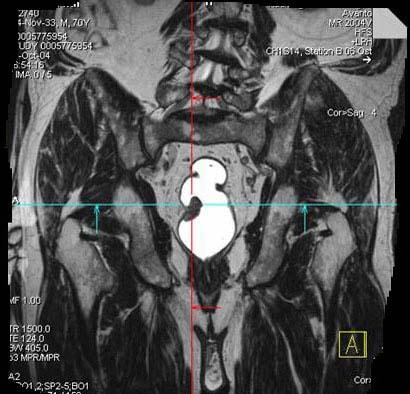

问题 男,70岁,下腹部腹胀、腹痛、排便困难,逐渐加重,MRI示直肠内不规则充盈缺损,请选择最佳诊断结果 ( )

选项 A.直肠息肉 B.直肠癌 C.直肠间质瘤 D.直肠转移瘤 E.直肠淋巴瘤

答案 B